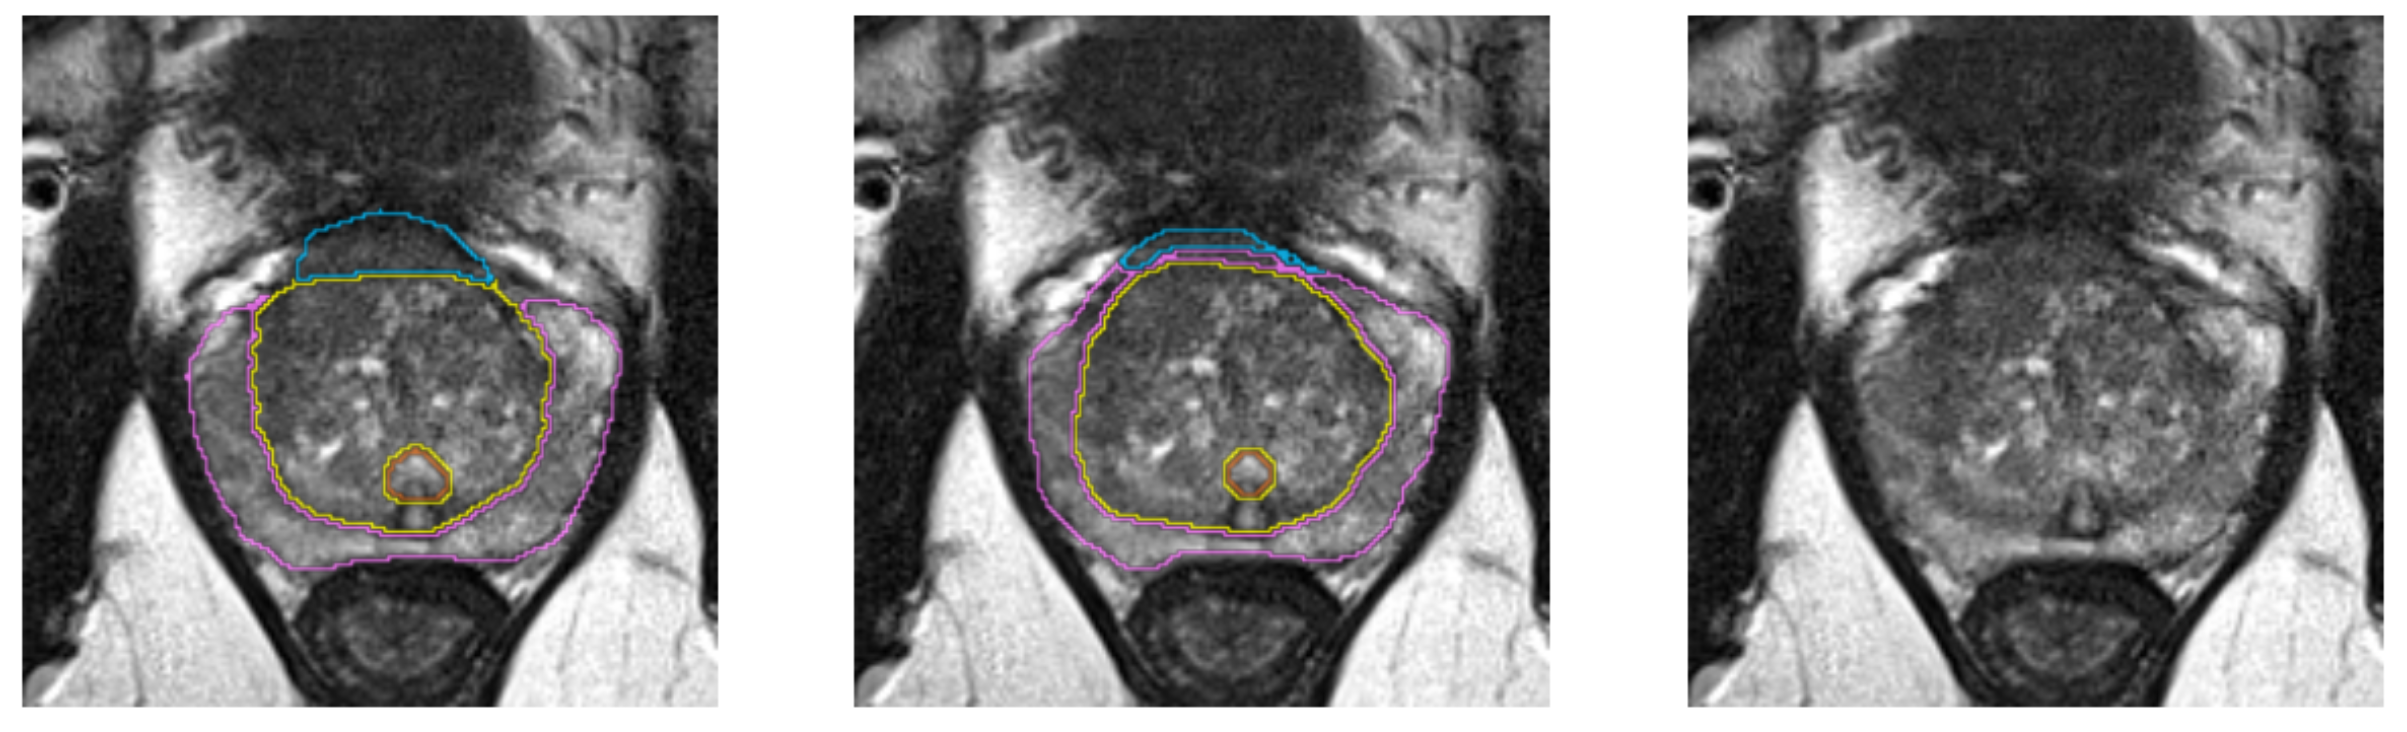

Multi-Label segmentation of anatomic prostate zones in MRI

The goal of this project is to evaluate and extend variants of a volumetric CNN for multi-label segmentation of prostate zones in MR images. The prostate zones are essential for lesion classification and therapy planning. After successful segmentation, a sector map could be extracted that is used for PI-RADS reporting. This has the potential to automate and better standardize prostate lesion location reporting. This project is a continuation of the project that we started in last Winter Project Week. We already have results, but especially in one zone, the algorithm does not work very well and is not stable.

- Find a way to stabilize outcomes for AFS (more regularizer, data augmentation) and then start to make the network deeper

Illustrations